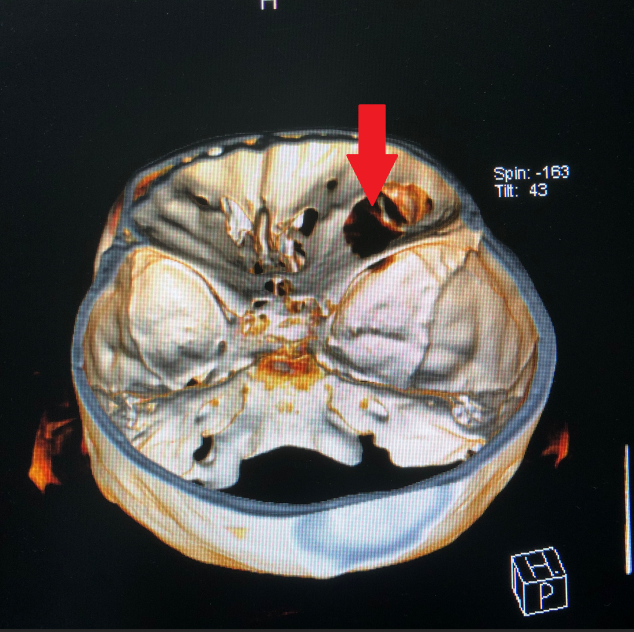

患者王女士,79岁,女性,2周前出现右眼疼痛,眼球突出,随后眼痛逐步加重,右眼视力急剧下降。在当地医院被诊断为眼眶内肿瘤,需手术治疗。但因患者眼眶肿瘤突破眼眶,向颅内生长,手术难度大。患者先后辗转多家医院眼科均无功而返。患者右眼疼痛难忍,最终选择到21点游戏攻略站 寻求最后的帮助。

21点游戏攻略站 神经外科团队接诊后对患者进行了全面检查,诊断为右眼眶肿瘤。因患者肿瘤向颅内生长,颅底及眼眶骨质已完全破坏,传统的手术方式不仅创伤大,更可能因为颅底结构无法完全重建导致患者脑脊液漏,引起颅内感染。神经外科联合眼科进行了手术方式的讨论,根据术中可能出现的各种情况其制定了详细的治疗方案,认真完善术前准备后,于2018年12月24日成功为其开展“完整切除颅内外沟通瘤并颅底眼眶重建修复手术”,手术过程非常顺利,术后患者无视神经损伤,视力较术前明显改善。目前患者已康复出院。